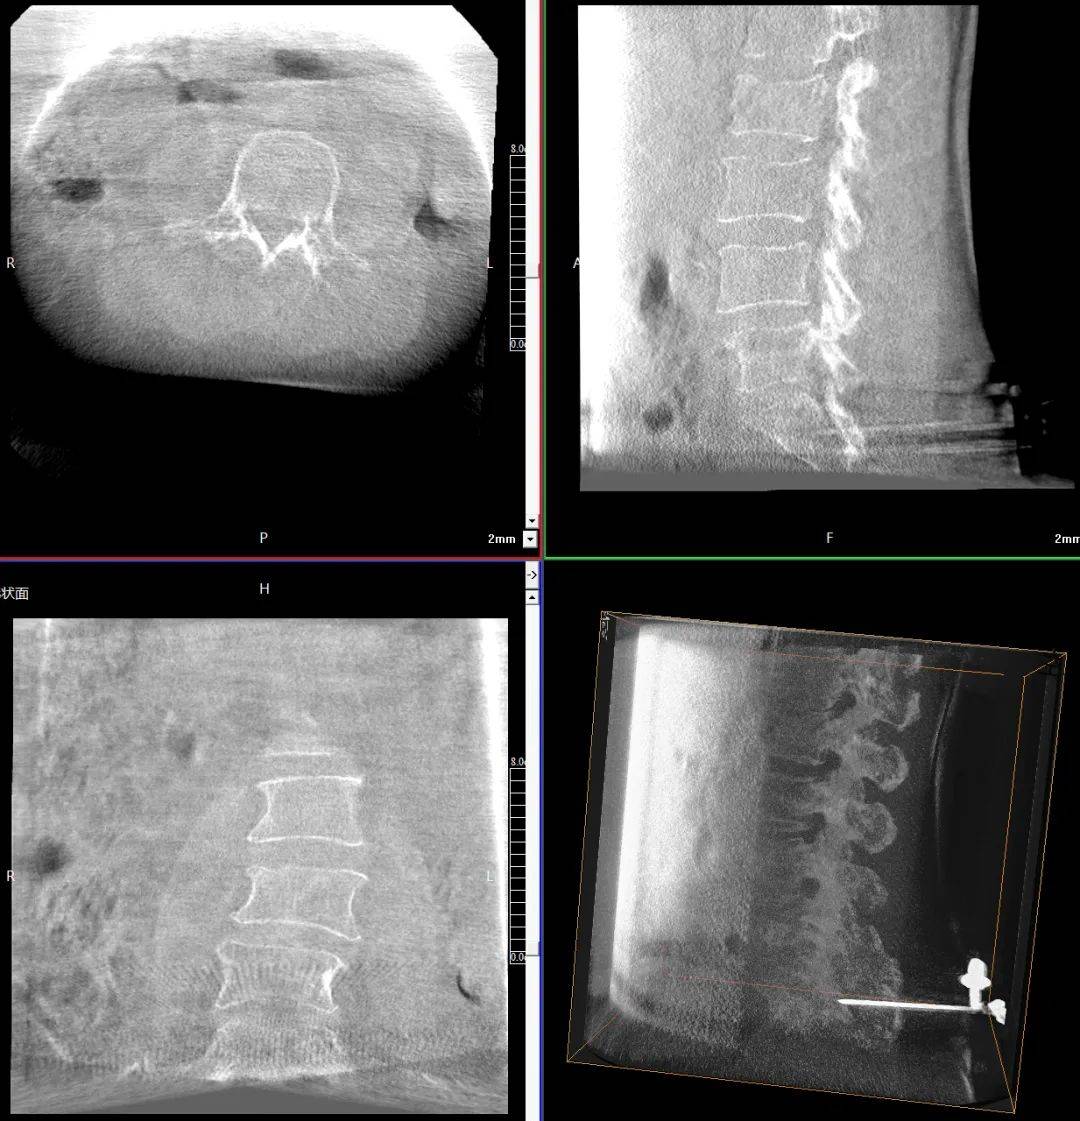

臨床表現(xiàn):患者主訴腰背部劇烈疼痛,活動(dòng)受限;查體證實(shí)腰背部局部壓痛、叩擊痛明顯,尤其在受累椎體區(qū)域;影像學(xué)檢查顯示多節(jié)段椎體壓縮性骨折,椎體高度明顯降低,椎體形態(tài)不規(guī)則,椎體扭曲畸形,椎弓根狹窄。

患者術(shù)前影像

手術(shù)指征:疼痛難以耐受,保守治療(如臥床休息、止痛藥物等)效果不佳;多節(jié)段椎體壓縮性骨折,椎體高度明顯降低,脊柱穩(wěn)定性受損。